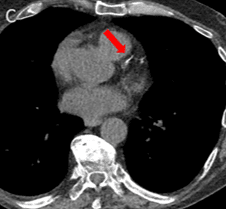

Coronary artery calcium becomes visible in the SpectralDR bone image and is confirmed on CT.